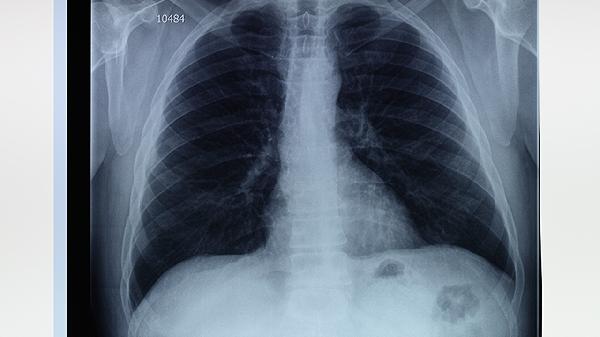

肺大疱的治疗方法主要有哪几种

肺大疱的治疗方法主要有保守观察、药物治疗、胸腔穿刺抽气、胸腔闭式引流、肺大疱切除术等。